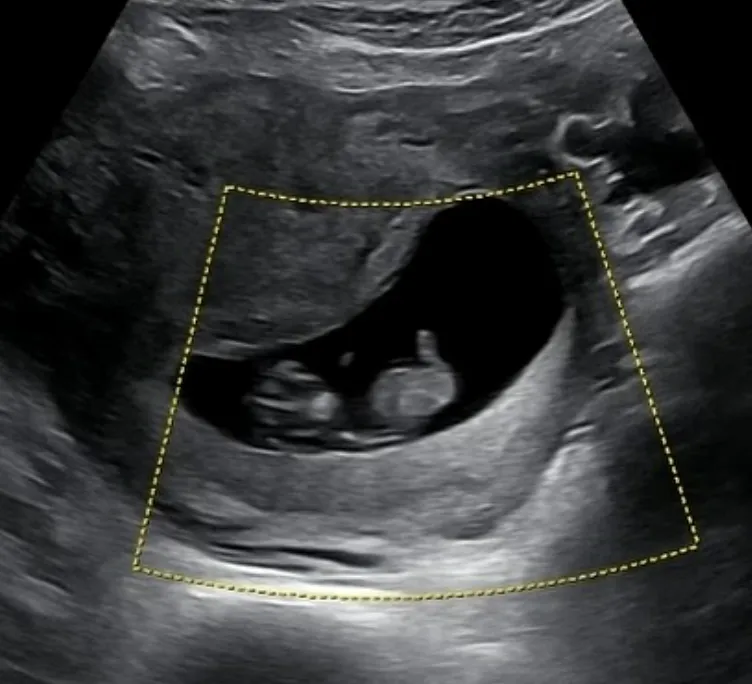

8일 KCM은 자신의 인스타그램에 “오늘 발매될 노래 ‘그댄 내게 가장 예뻐요’처럼 이 세상에 또 하나의 가장 예쁜 선물이 찾아왔다”며 초음파 사진을 공개했다.

이어 “저 셋째 아빠 된다. 축하해 달라”며 “이 곡은 셋째 소식 듣고 아내와 가족들이 너무 예쁘고 고맙고 사랑스러움에 영감을 받아서 만들었다”라고 덧붙였다.